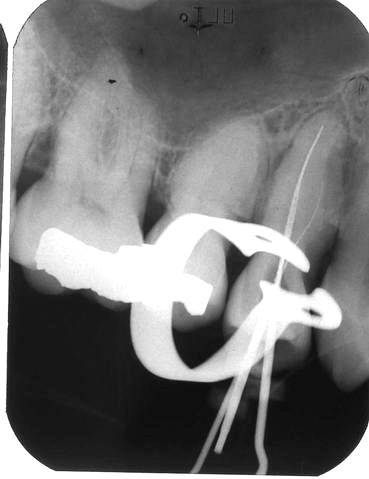

Bij de endodontische behandeling wil een dikkere vijl  niet verder dan tot de wortelsplitsing. Bij goed manipuleren met iets voorgebogen dunnere handvijlen lukt het dan vaak wel om één van de kanalen toegankelijk en doorgankelijk te maken. Meer problemen geven dan de andere kanalen na de splitsing. De behandelmicroscoop maakt het preparen van dergelijke kanalen een stuk gemakkelijker omdat de verschillende kanalen ter plaatse van de splitsing zichtbaar zijn te maken. Ook het vullen van diepe kanalen is een stuk eenvoudiger als men de beschikking heeft over een behandelmicroscoop.